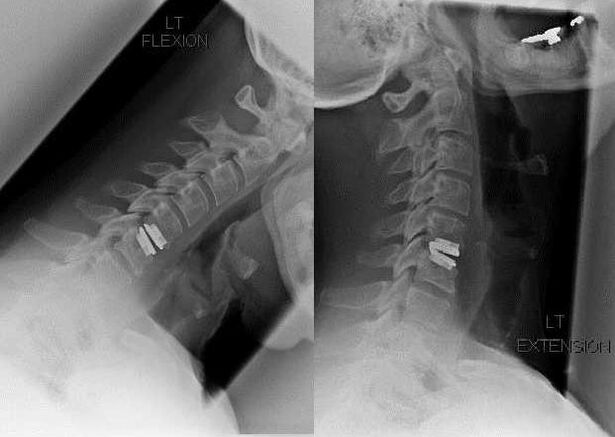

Chirurginė intervencija

Chirurginės intervencijos indikacijos yra konservatyvaus gydymo neveiksmingumas, taip pat gimdos kaklelio osteochondrozės komplikacijos, pavyzdžiui, diskogeninė mielopatija, slankstelinės arterijos sindromas ir radikulinis sindromas. Nugaros smegenims, kraujagyslėms ir stuburo šaknims išspausti atliekamos šios operacijos:

Operacijos metu gali būti išpjauti kaulų fragmentai ir raiščiai, visiškai arba iš dalies pašalinti tarpslanksteliniai diskai. Dėl mažų išvaržos iškilimų dažnai atliekamas disko branduolio garinimas lazeriu.

Po stuburo struktūrų ekscizijos dažnai reikia stabilizuoti stuburo judesio segmentus suliejant stuburą arba įrengiant kaulo ir odos autotransplantatus.